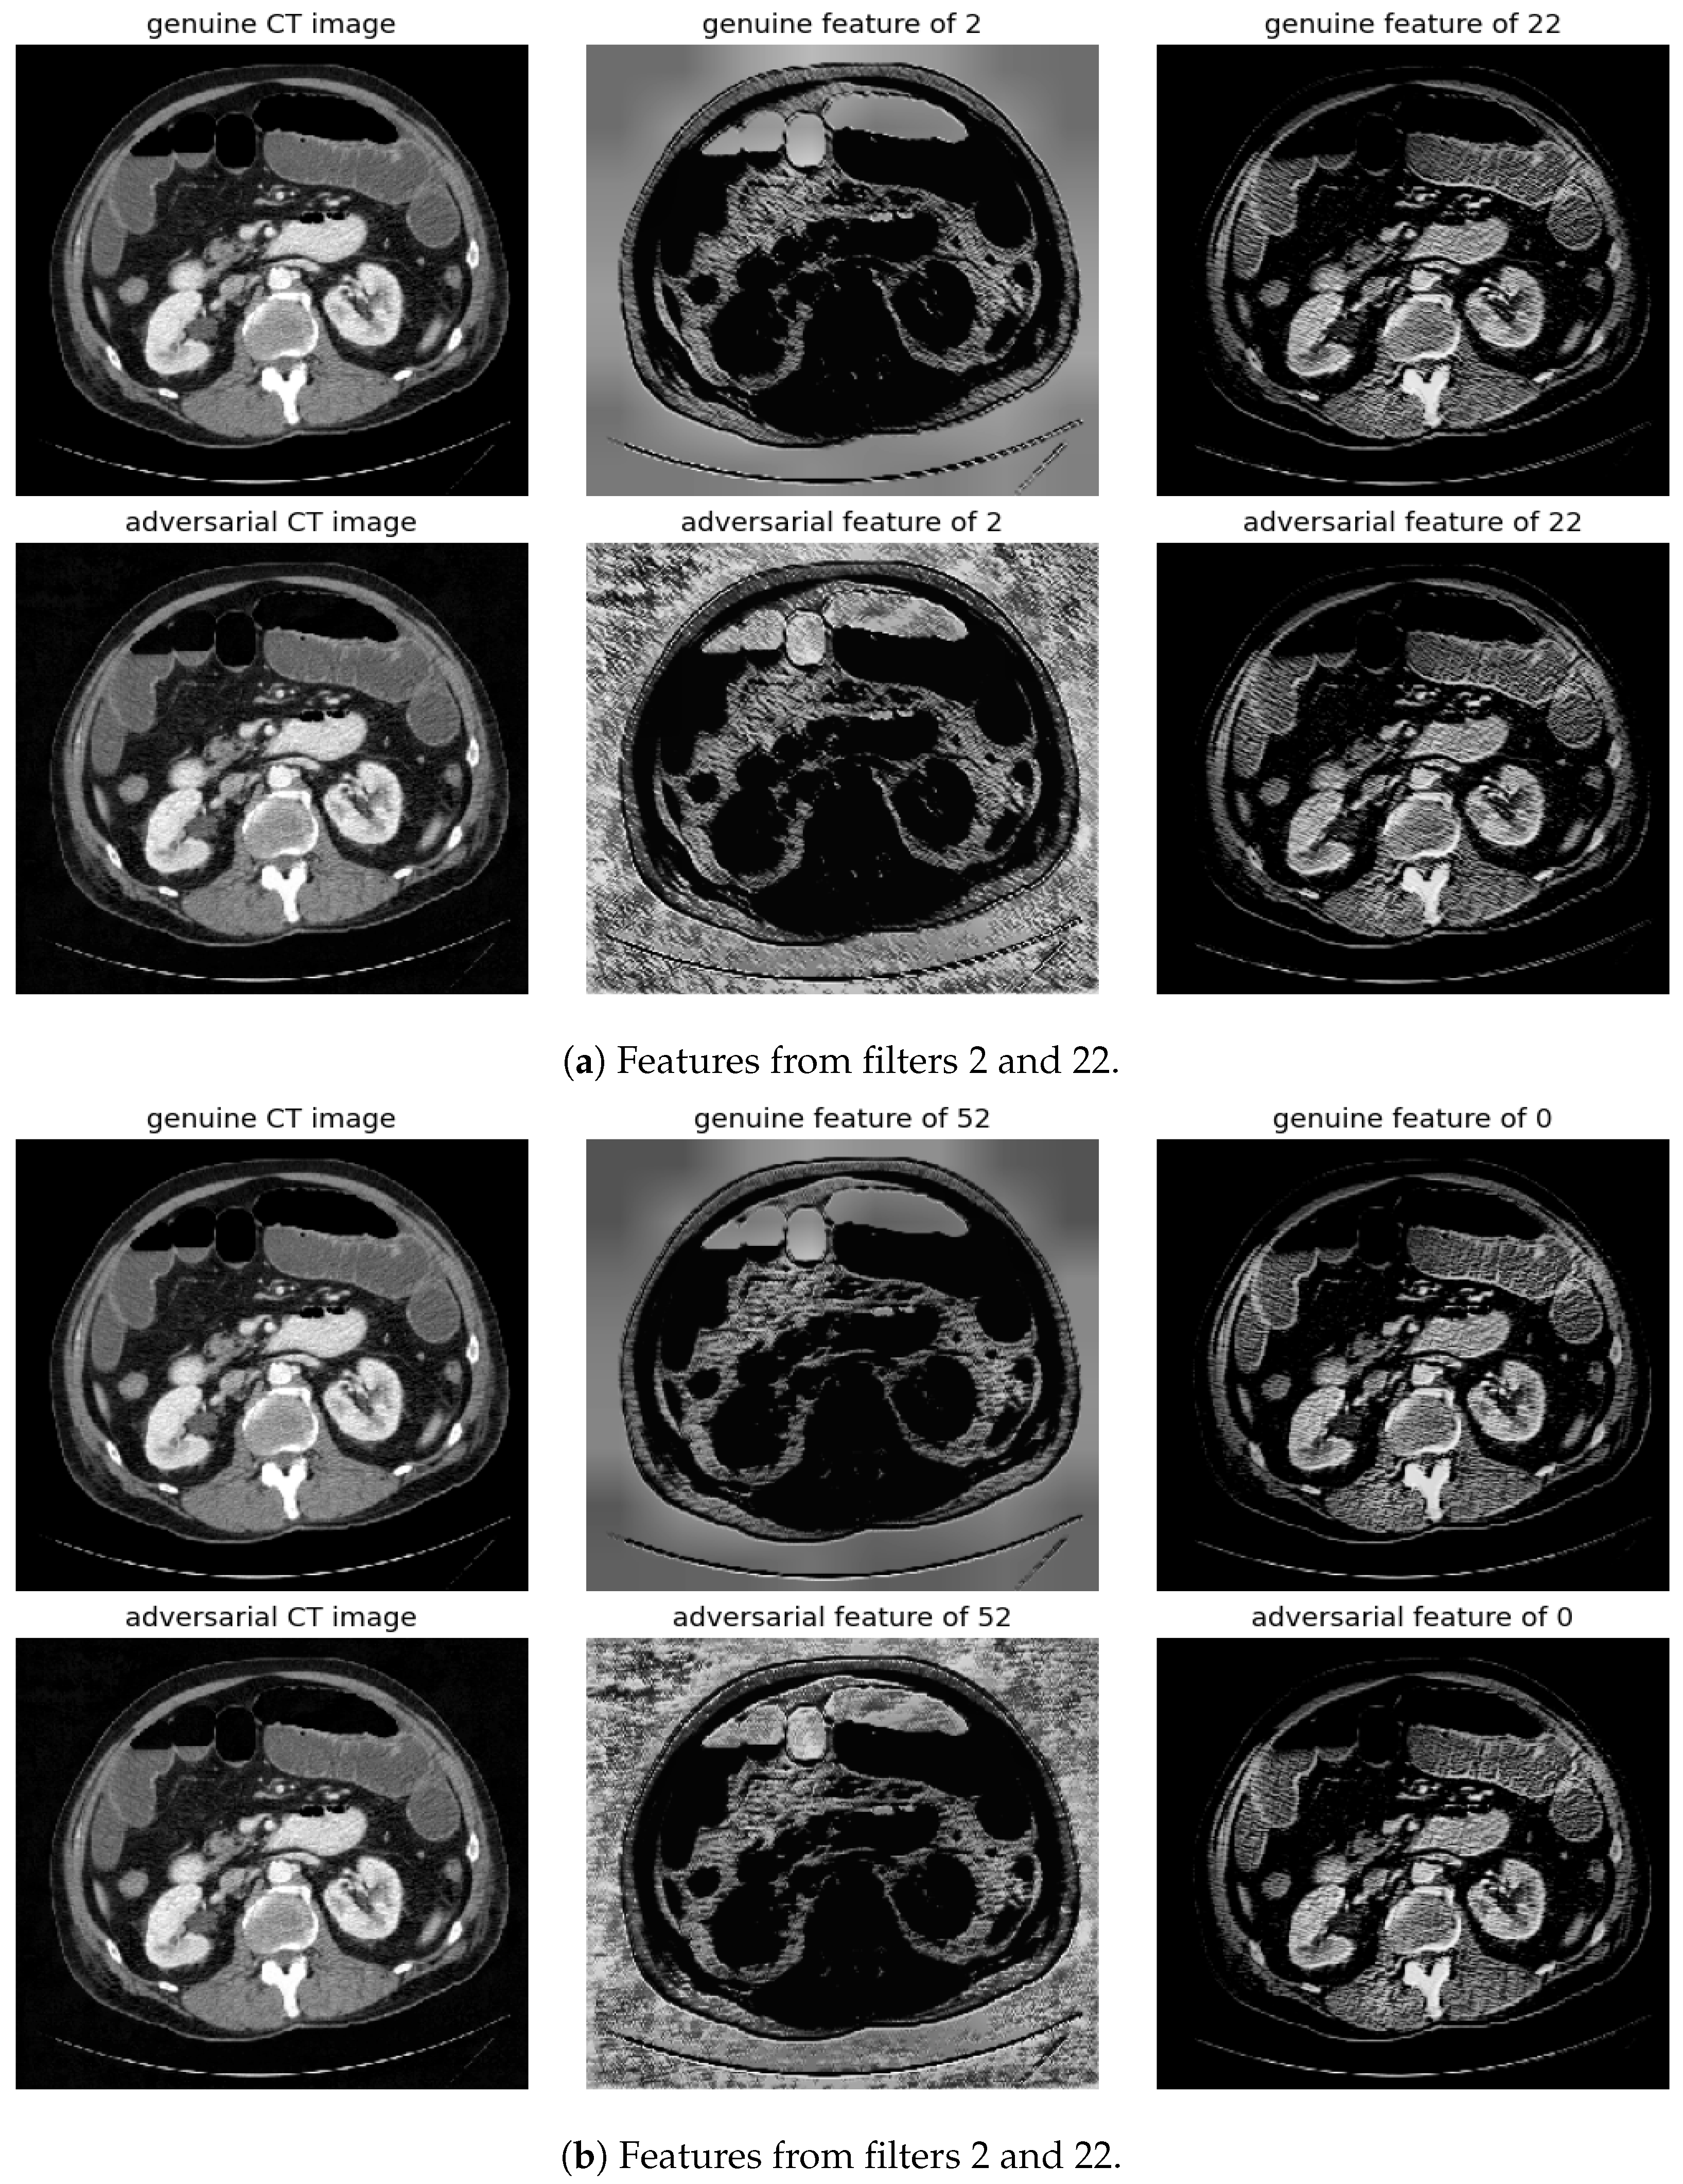

Randomly selected genuine CT samples, alongside their adversarial versions, are displayed in Figure 9, Figure 10 and Figure 11. The adversarial samples were generated using FGSM, BIM, and SMIA attack methods, each with an epsilon of 0.01. While BIM and SMIA used 5 iterations, FGSM did not. These samples represent the most challenging scenarios for human visual detection. Despite the modest epsilon value, as indicated in Table 3, the adversarial attacks have a subtle but pronounced effect. Such slight modifications can lead to major diagnostic inaccuracies potentially impacting patient care.

Figure 11.

Visualization under SMIA Attack: Comparison of features from the first layer between genuine and adversarial samples for the most sensitive (filters 2 and 52) and least sensitive (filter 22 and 0) filters.

To address this, histogram equalization as feature post-processing is applied. The visual representations underscore that while genuine and adversarial samples might appear similar to the naked eye, post-processing brings forth distinct feature differences when employing the most sensitive filters from 2 and 52. Perturbations, especially noticeable in the background of the adversarial samples, are frequently highlighted by these filters. Conversely, features processed with filters from 22 and 0, deemed less sensitive in prior analyses, fail to offer a stark visual contrast.